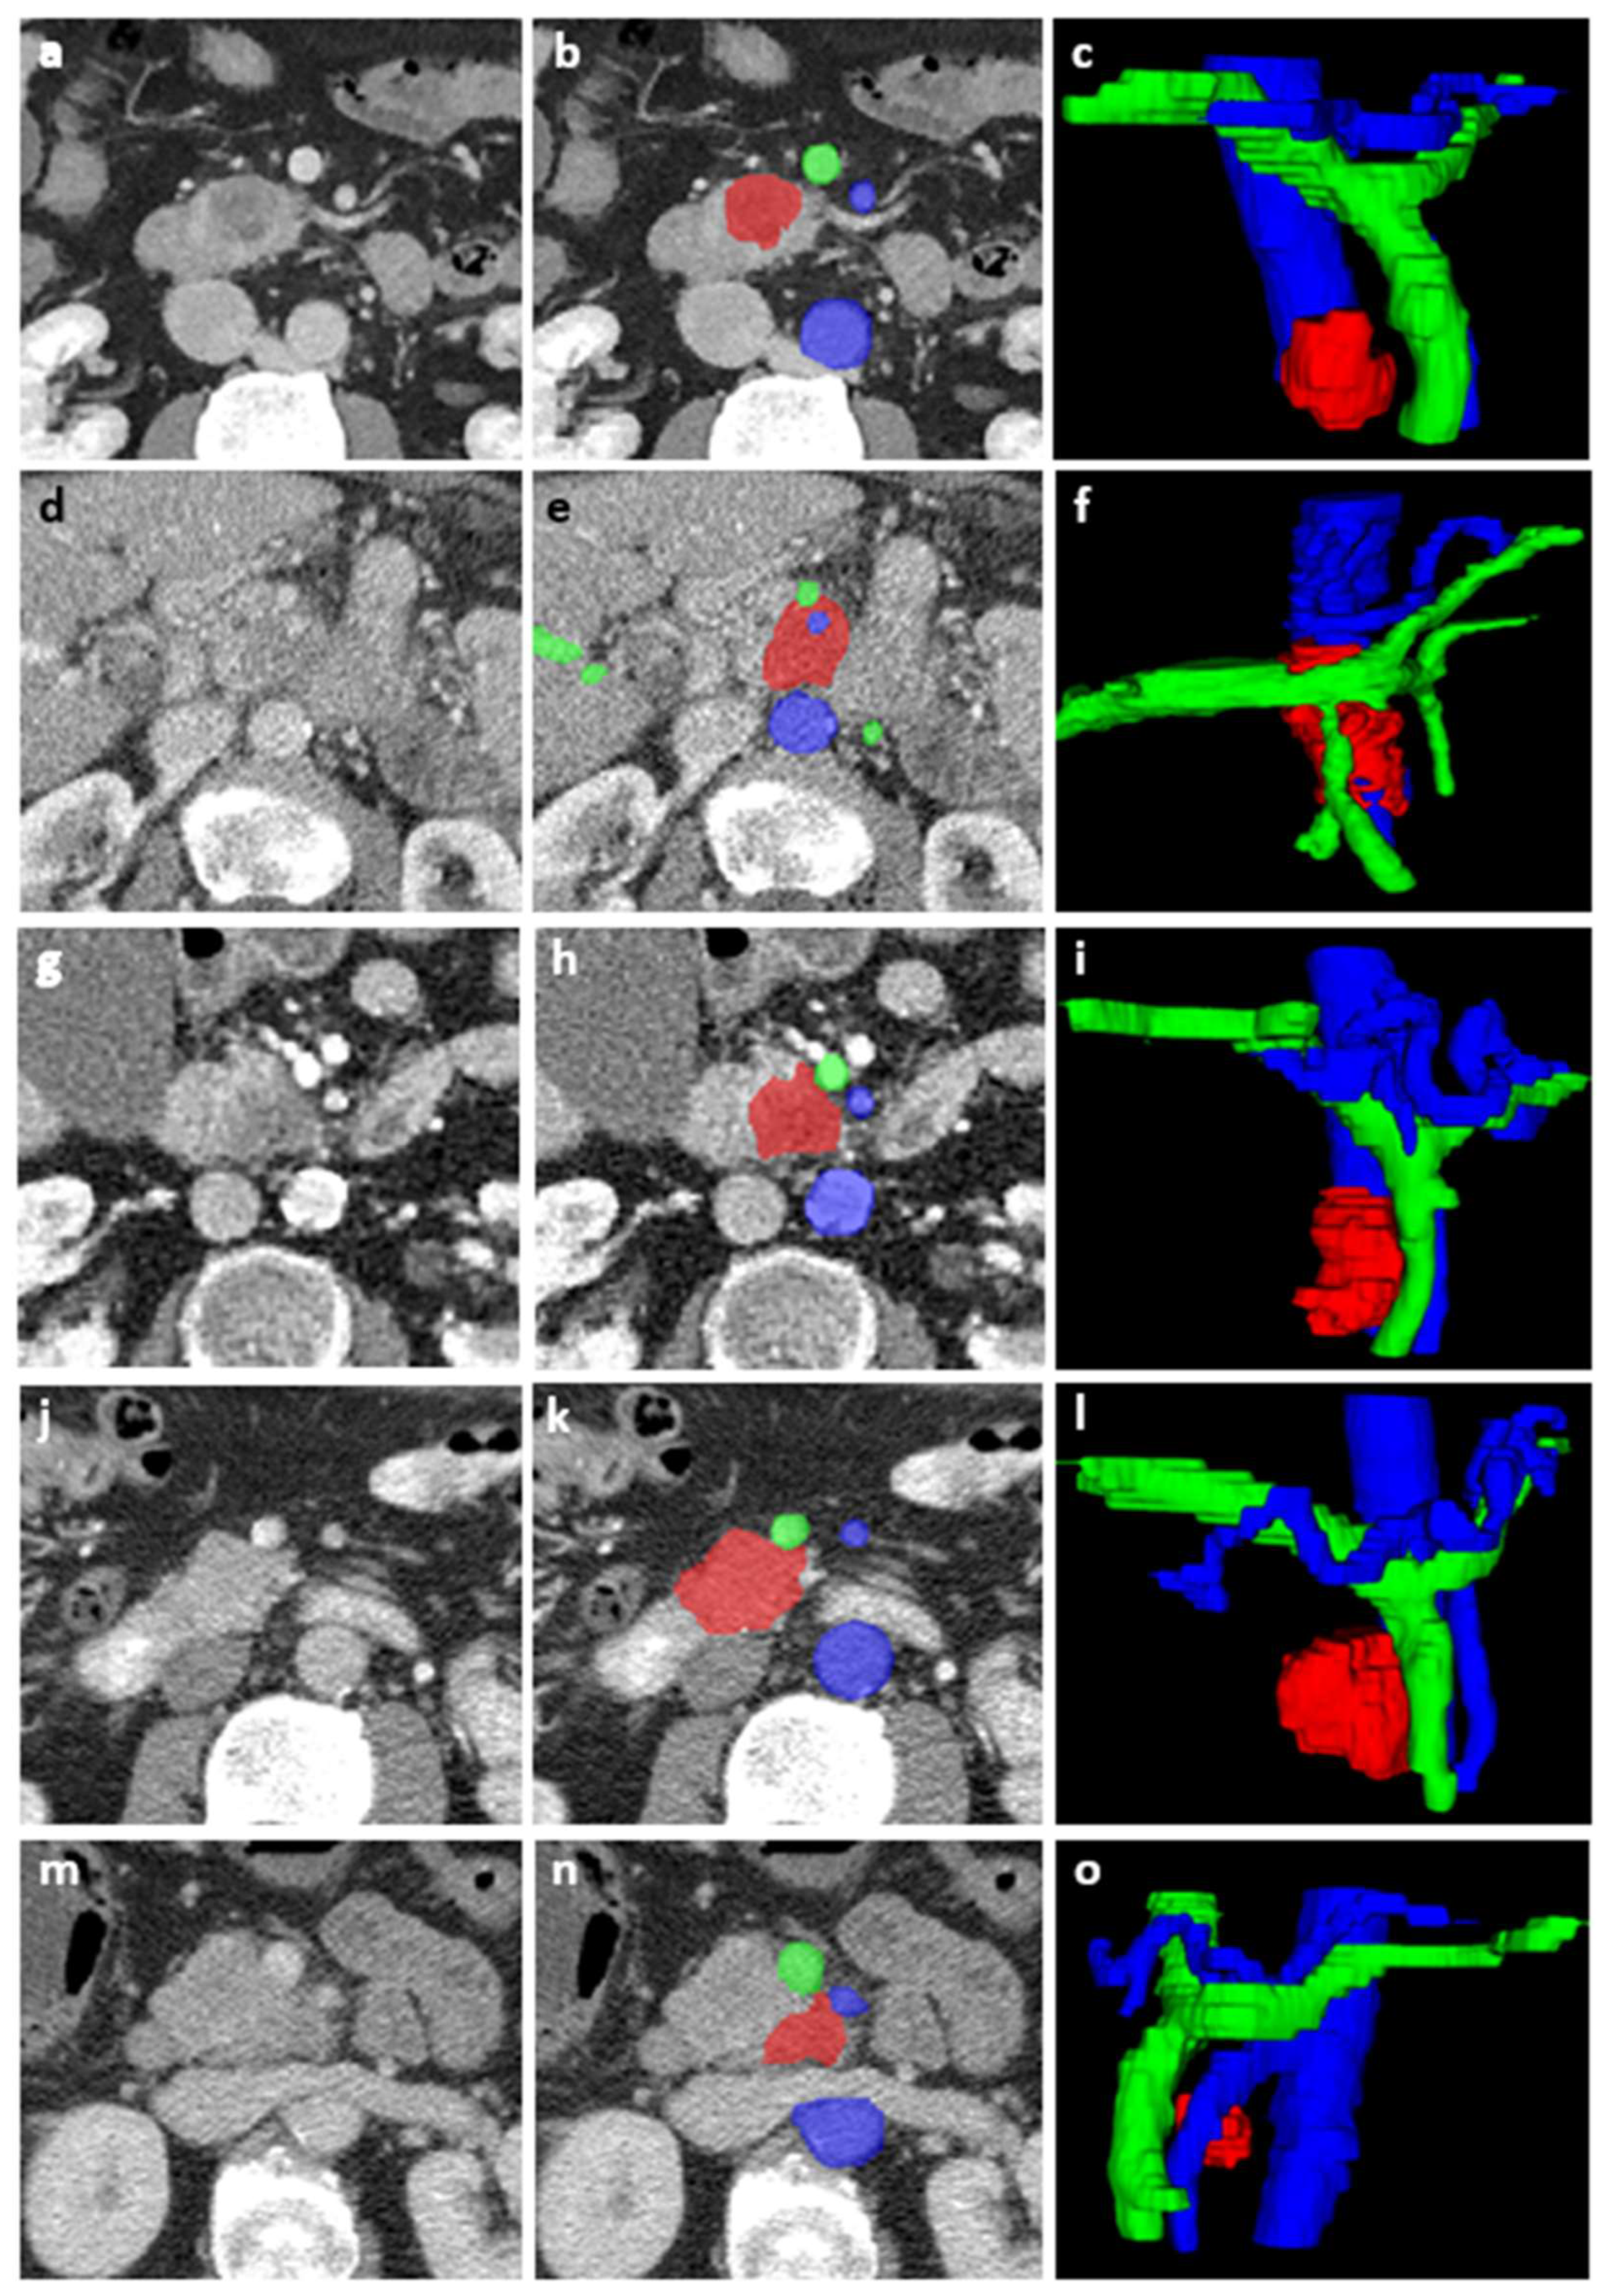

2.3. Image Acquisition and Segmentation

2.4. Tumor Features

2.5. Vessel Features